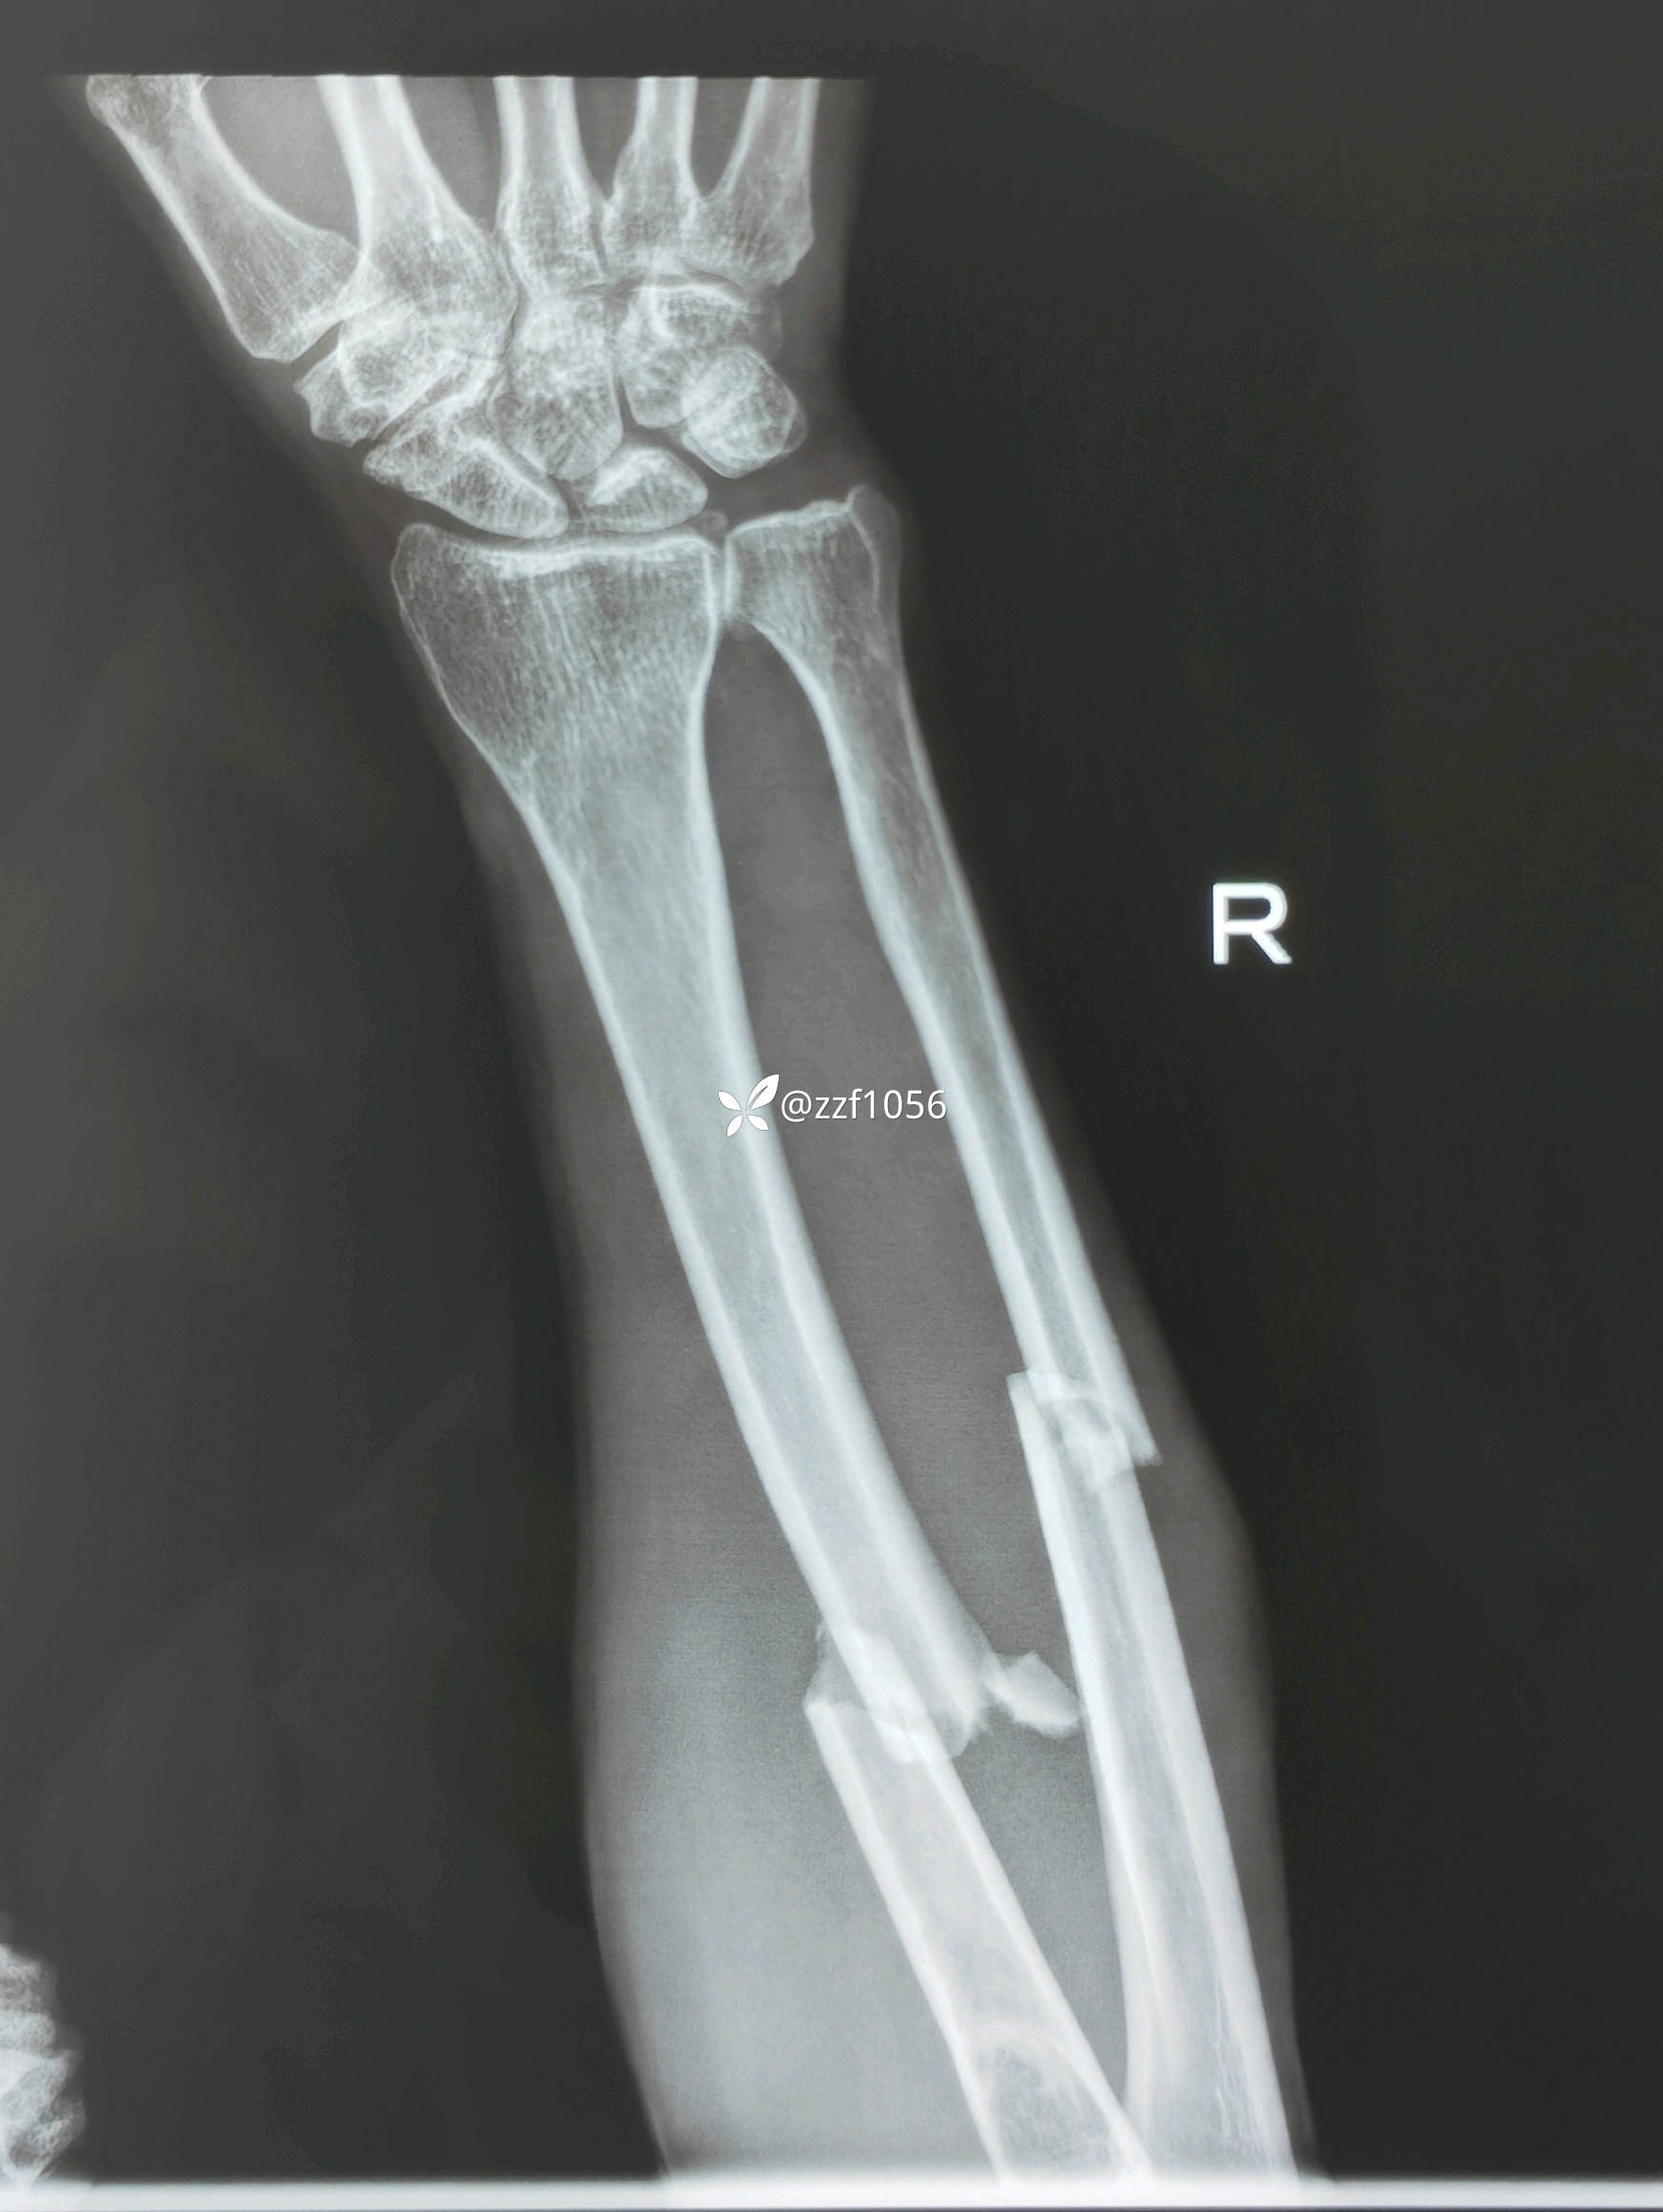

患者中年男性,五保户,聋哑人,骑车碰伤致右前臂肿痛畸形1小时余急诊入院。

入院诊断:右侧尺桡骨干双骨折

完善检查,第二天手术